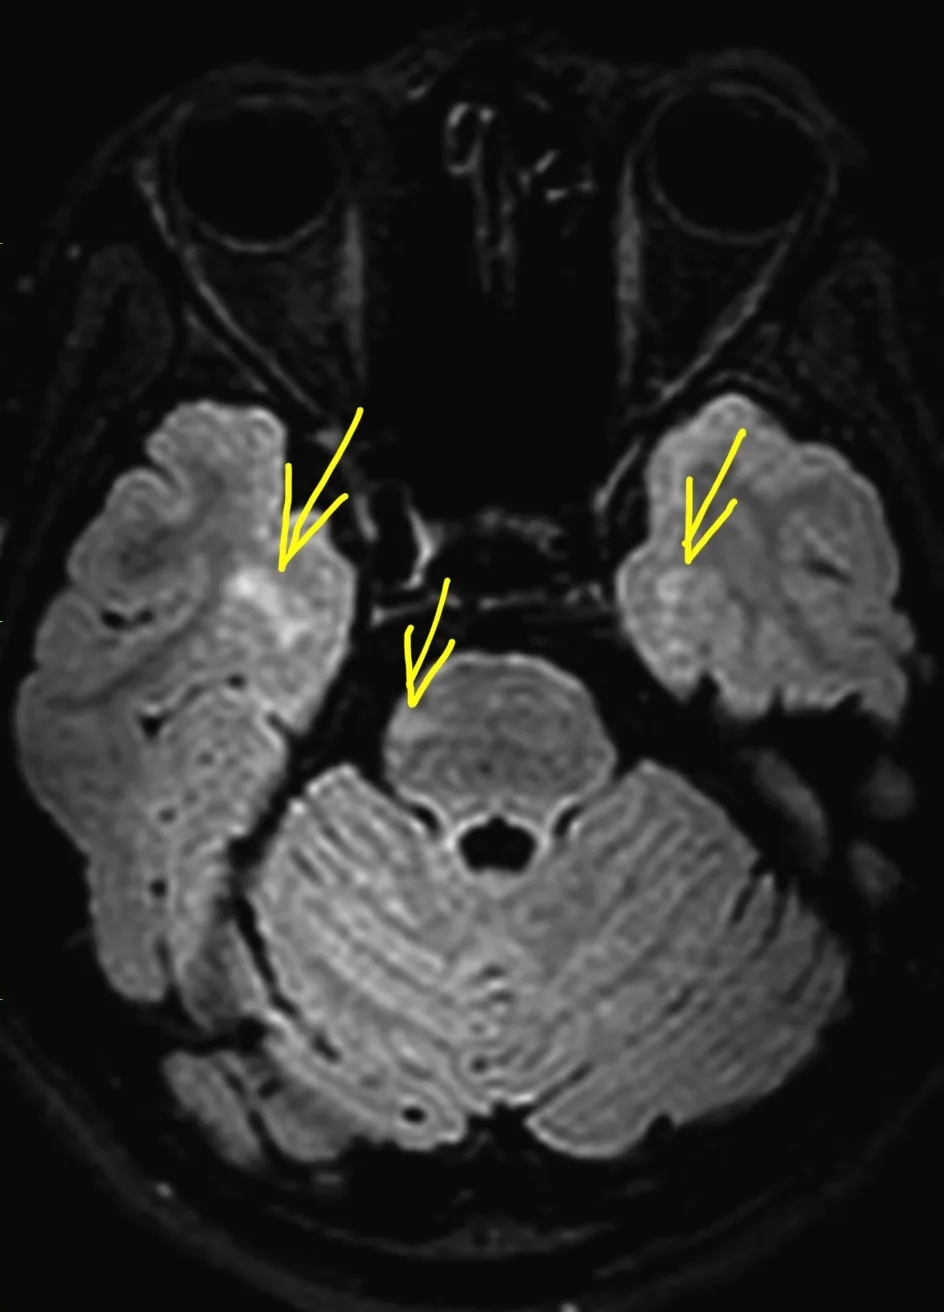

Мужчина 35 лет, месяц назад упал с высоты двух метров, сейчас не полностью ориентирован в месте и времени. Типичная (кроме мозжечка справа) картина травматического аксонального повреждения 3 степени (с поражением ствола). Множественные мелкие точечные и линейные микрокровоизлияния, вокруг части из них видны глиоз/отек. А вот в мозжечке, реально, нечасто такое увидишь. Но бывает. Типа, как вот здесь: